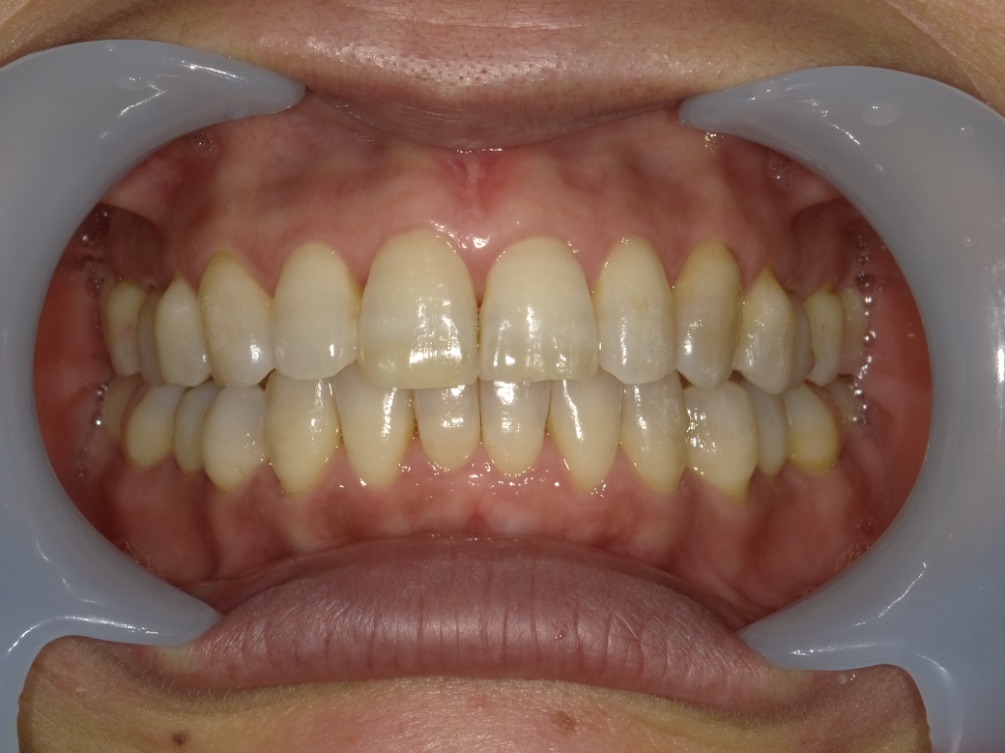

AFTER

正面